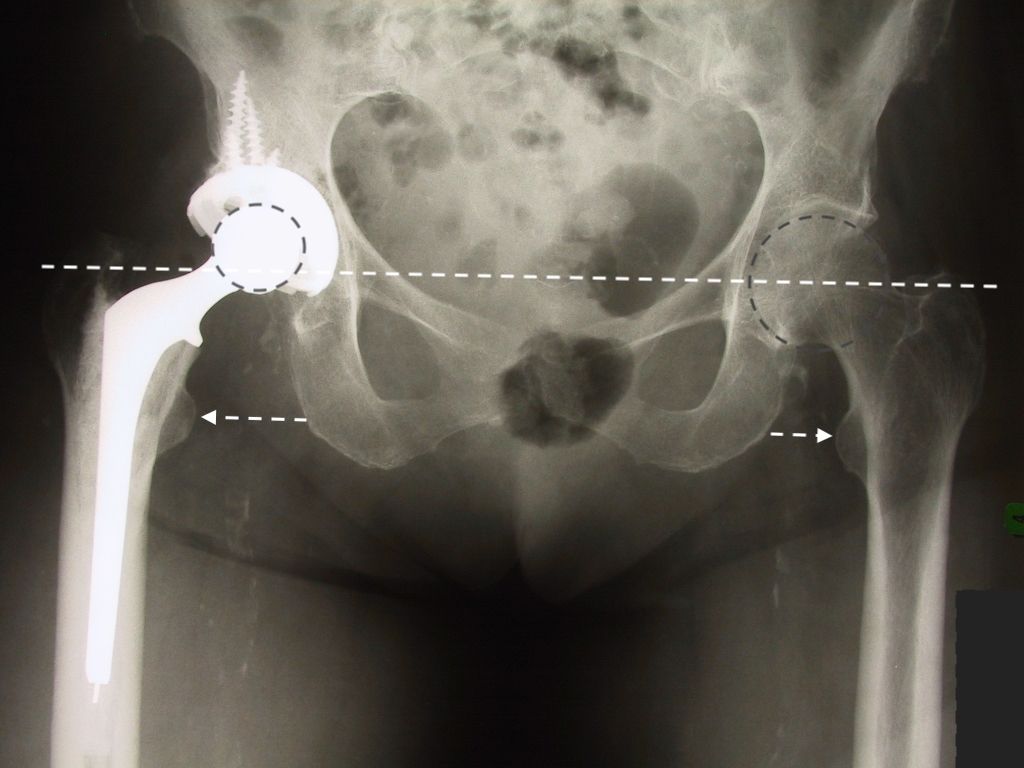

Dislocation is one of the leading causes of THA revision with a variable incidence in the literature. However, calculating the exact rate is a complex matter as closed reductions may remain undetected. Hermansen et al. sought to find the true cumulative incidence of dislocation in 30,000 THAs in the Danish registry and reported a rate of 3.5%[11]. The primary arguments in favour of using an LDH are a wider impingement-free range of motion and a reduced risk of dislocation due to increased jump distance and the larger head volume to displace (Figure 6).

Zijlstra et al. analysed 160,000 THAs from the Dutch arthroplasty register and found that the cumulative risk of dislocation was significantly higher in 22–28mm heads (1.1%), compared to >36mm heads (0.5%)[12-14]. In our experience of more than 3500 CoC LDH THAs implanted since 2011, we encountered five (0.14%) early postoperative dislocations. Four were successfully treated with closed reduction, and one had recurrent dislocations requiring revision surgery. Once instability is of lesser concern, leg length adjustment and femoral offset restoration can be performed with more ease (which helps to achieve goal #1). Using intraoperative measurements or computer/robotic assistance, the surgeon can focus on anatomy restoration without the fear of instability. Knowing that patients would prefer a shortened leg to an elongated one, we favour a shorter one when in doubt between two head lengths.

Using an LDH THA allows unrestricted movement after THA, for all types of surgical approaches. Vendittoli’s group in Canada does not impose any postoperative ROM restrictions for the posterior surgical approach, as it simplifies the patient education process, boosts their confidence during rehabilitation, and facilitates bilateral procedures[15,16]. LDH monobloc DM is especially interesting for many older women with large thighs and a small acetabular cavity (<50mm, Fig. 7).